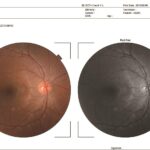

TRUE COLOR FUNDUS PHOTOGRAPHY

OCT 500 has an integrated full color fundus camera. With one touch, you can simultaneously acquire a posterior OCT image and a fundus image. This fundus photo can help to locate quickly the exact position of the OCT-scan and provide additional information for diagnosis of various retinal diseases.

PERIPHERAL FUNDUS PHOTOGRAPHY

The 9-point fixation target in the 3D OCT-1 allows the operator to make nine different color fundus photos and compose them into one total overview of the fundus. With optional software, a panoramic or mosaic overview can be created.